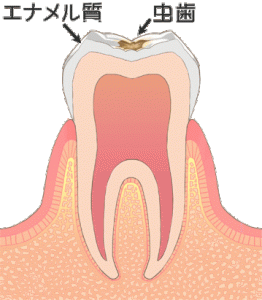

エナメル質の虫歯(C1)

基本的にしみる、痛い等の症状はありません。 歯の表面上に虫歯による着色があり、エナメル質が少し溶けている状態です。 場合により、溶けているところに汚れがたまりやすかったり、見た目が悪く気になったりということがあります。

基本的には丁寧な歯みがきを心掛けて、定期検診ではの状態をチェックしていきます。 必要に応じて、フッ素を塗るのも有効な手段です。 食べ物がたまりやすかったり、見た目上気になる場合は、小さな虫歯を削り、シーラントやコンポジットレジン修復(白いプラスチックのつめもの)を行います。